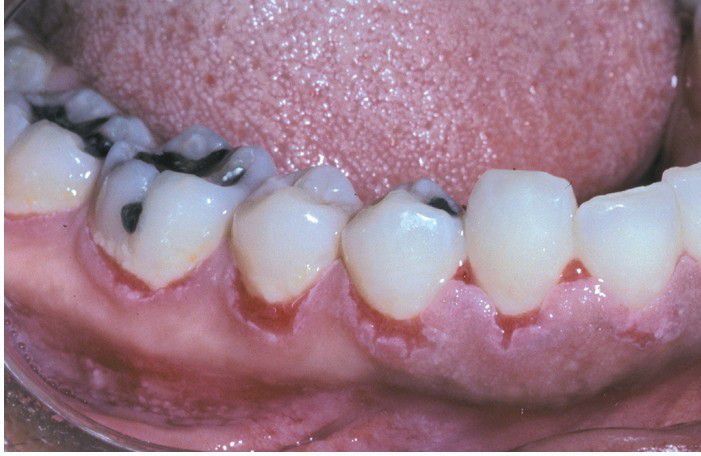

Pemphigus Vulgaris.

Multiple erosions affecting the marginal gingiva.